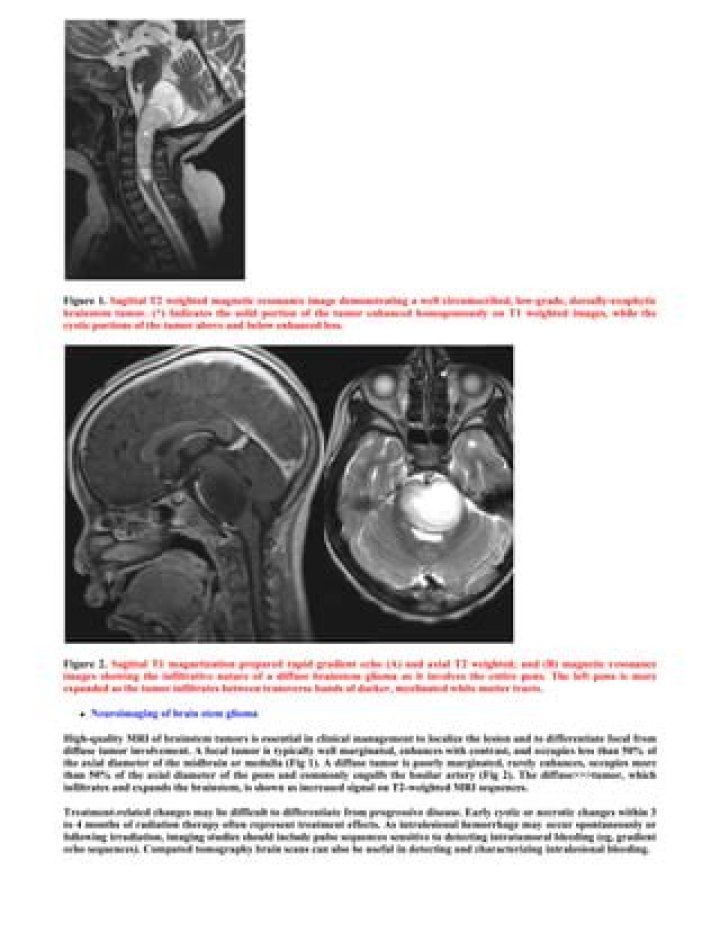

What does a glioma look like on MRI?